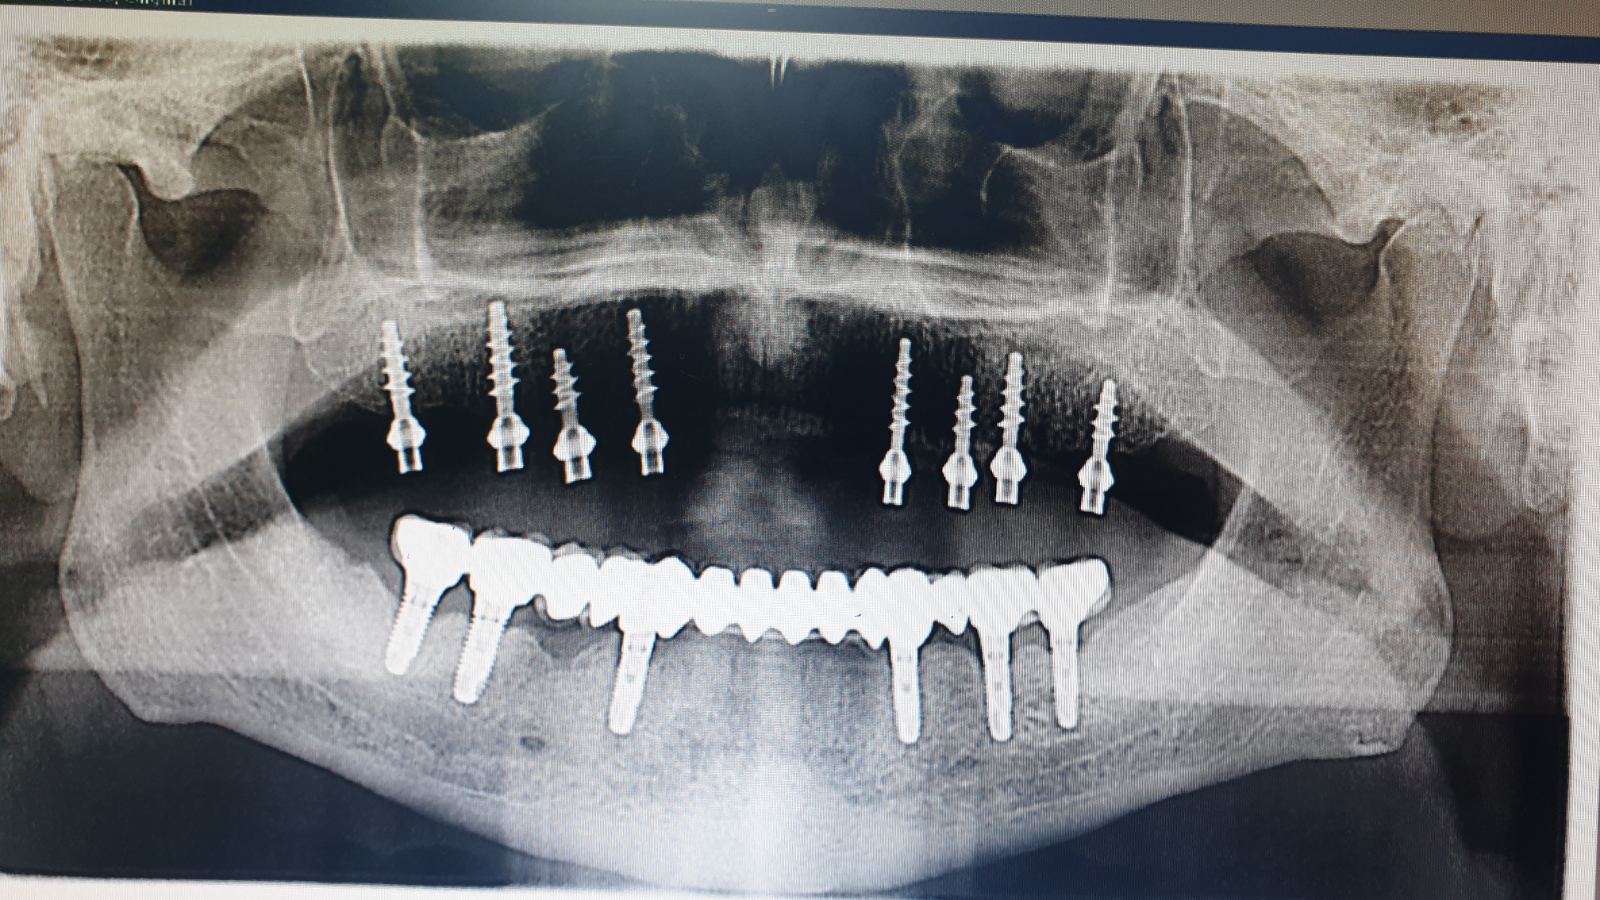

Имплантот е титаниумски завртка, хируршки поставена во вилицата, која ја презема функцијата на природниот корен на забот. Врз него потоа се додава индивидуална протетска изработка која по изглед и чувство е слична на природен заб.

Во нашата ординација, имплантолошките процедури се изведуваат со напредна 3D-дијагностика и минимално инвазивни техники, што овозможува: